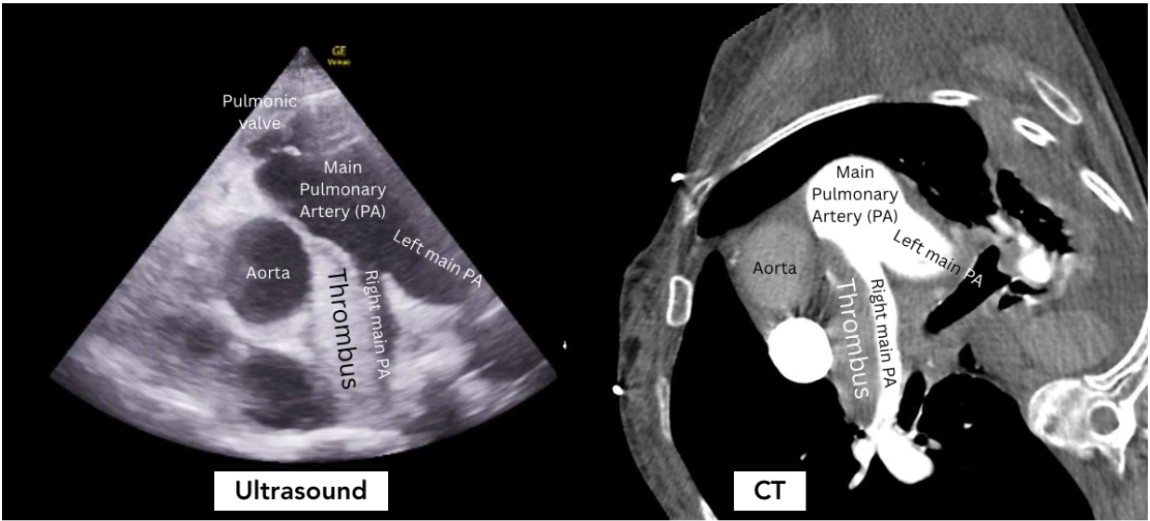

An 82 year old female presented to the Emergency Department (ED) for 1 week of left leg swelling and shortness of breath. In the ED, she was hypoxic to 88% requiring 30 liters per minute high flow nasal cannula and hypotensive to 69/44 mmHg requiring 5mcg/min norepinephrine drip. On exam, she was tachycardic to 127 beats per minute and tachypneic to 24 breaths per minute with labored respirations. Her lungs were clear to auscultation and she had bilateral 2+ leg edema with the left mildly greater than the right. Point-of-care transthoracic echocardiography showed a large non-mobile hyperechoic thrombus extending from the main pulmonary artery (PA) bifurcation and into the right main PA with right ventricular (RV) dilation. Computed tomography with contrast of the chest showed a large hypodense nonocclusive filling defect extending from the main PA into the right main PA which indicated acute pulmonary embolus (PE) with evidence of right heart strain (RHS) – the same diagnosis made within minutes by bedside echocardiography.

Figure 2

This case highlights the value of bedside echocardiography in the definitive diagnosis of a massive pulmonary embolism. Traditional point-of-care transthoracic echocardiography evaluates for indirect signs of acute PE through the identification of RHS 1,2. Generally, this is an assessment in parasternal long and apical views for RV dilation, McConnell’s sign (right ventricular free wall akinesis with sparing of the apex), and/or abnormal Tricuspid Annular Plane of Systolic Excursion (TAPSE <17mm is abnormal)2. The parasternal short view can show septal flattening (“D sign”) and RV dilation. More recent publications have demonstrated the utility of diagnosing RHS through the identification of a systolic notching pattern or abnormal pulmonary artery acceleration time in a right ventricular outflow track (RVOT) view3. Our case illustrates the value of the RVOT view for direct visualization of a large pulmonary embolism, allowing the emergency physician to definitively make the diagnosis of massive pulmonary embolism at the bedside, without the patient ever having to leave the resuscitation bay. This view is obtained by placing the probe in the parasternal short axis view and fanning cephalad until the right ventricular outflow tract is visualized.